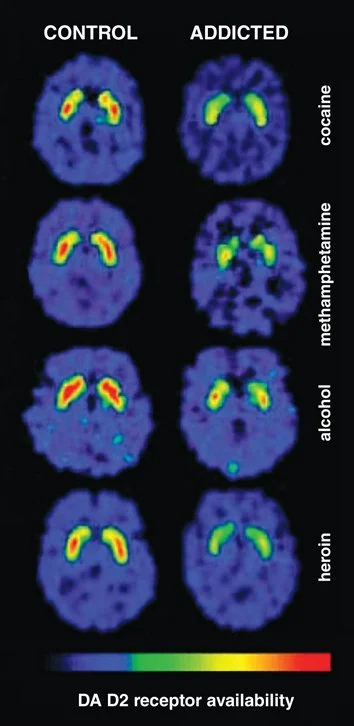

På hjärnavbildningar (PET) kan detta ses som en minskad tillgänglighet av D2-receptorer – vilket i praktiken innebär att hjärnans belöningssystem blir mindre aktivt, något som tydligt syns i jämförelser mellan “control” och “addicted”.

Minskad tillgänglighet av D2-receptorer vid beroende – synligt som lägre aktivitet i hjärnans belöningssystem jämfört med kontrollpersoner. Källa: PET-studier av dopamin D2-receptorer inom beroendeforskning (bl.a. arbete av Nora Volkow).